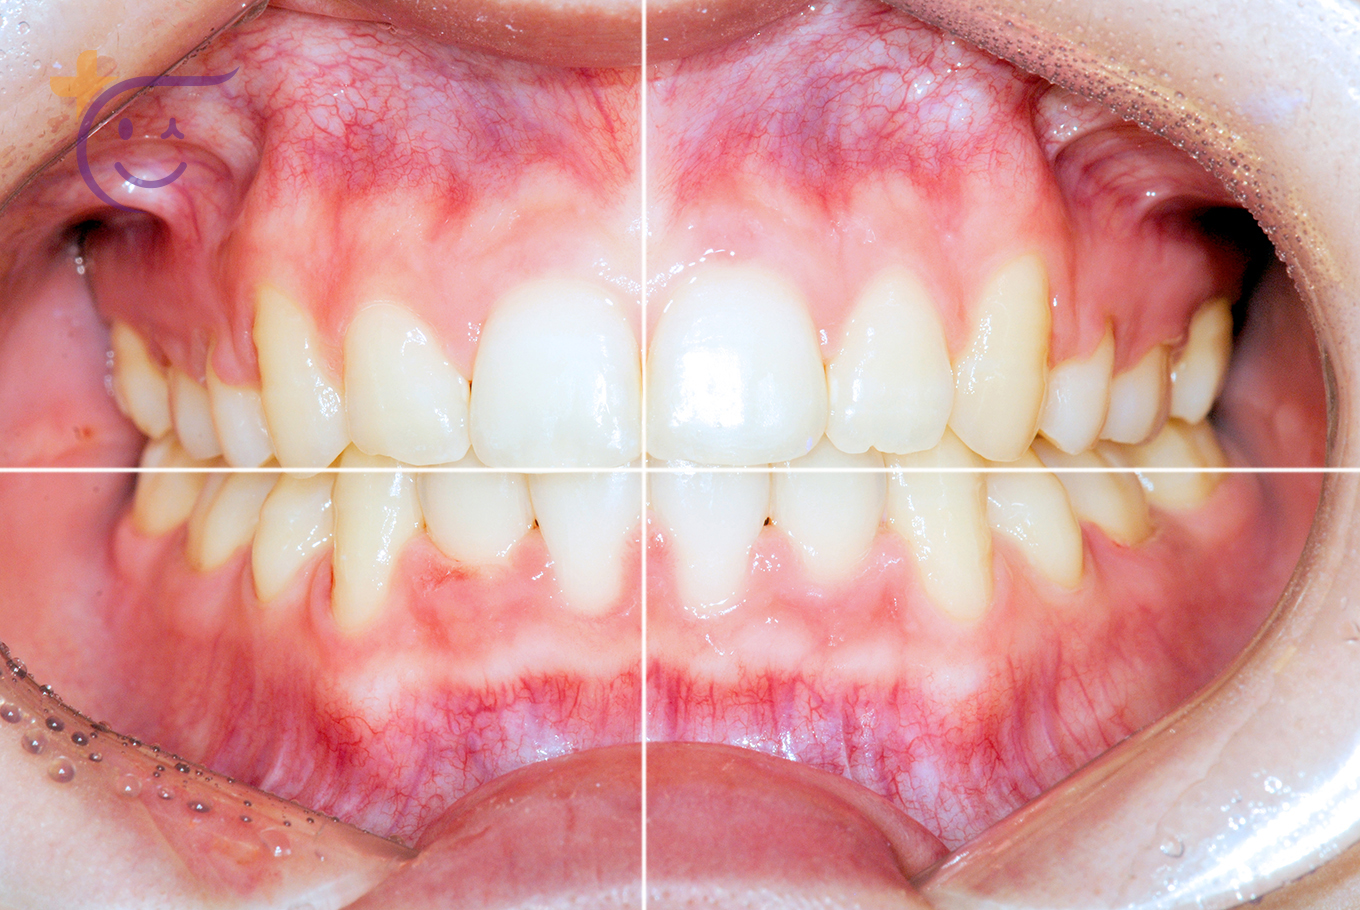

Harmony & Innovation

집중치료센터교정치료는 조화를 통해 얼굴을 혁신적으로 변화시킵니다.

얼굴과 치열의 조화와 균형이 아름다운 미소를 완성합니다.

연세플러스의 다년간 노하우는 수술없이 교정만으로도

더욱 세련되고 고급스런 외모를 창조합니다.